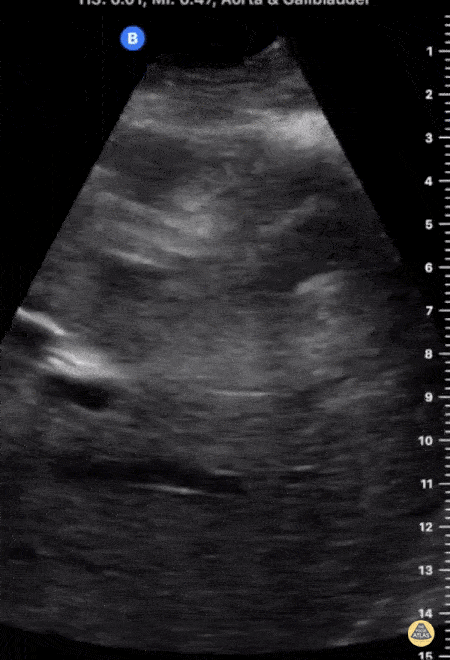

Biliary - Gallstone Stuck in GB Neck with Shadowing

This image demonstrates a large gallstone lodged in the neck of a distended gallbladder with posterior shadowing. There is no evidence of gallbladder wall thickening seen here. Jonny Wilkinson, Consultant in ICU and Anesthesia https://criticalcarenorthampton.com